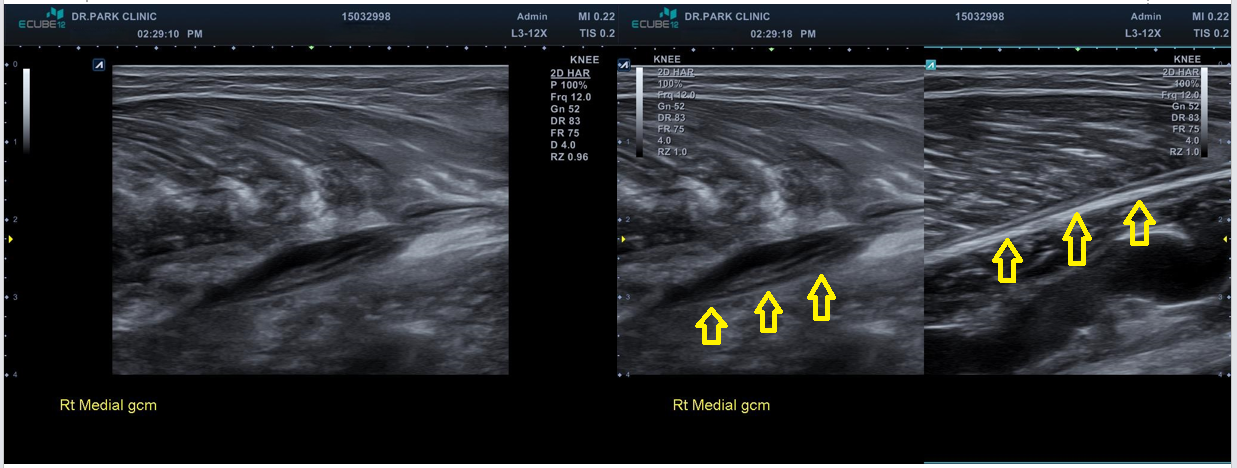

당산 정형외과, 당산역 정형외과, 영등포 정형외과안녕하세요 박상준원장입니다. 오늘은 운동하다가 종아리 근육이 파열된 환자 이야기를 해볼까합니다.나 : 어디가 불편하세요?환자 : 종아리가 아픕니다. 나 : 무슨일이 있으셨나요? 환자 : 며칠전에 농구하다가 종아리가 뜨끔했는데요... 그 이후로 계속 아프네요.. 농구하다가 갑자기 종아리 통증이 생겼다는 환자... 종아리를 살펴보니 우측 종아리 알통(비복근) 부위가 많이 부어있었습니다.나 : 보통 이런경우는 종아리 근육, 비복근 파열입니다. 검사를 좀 할건데요... x-ray 검사와 초음파 검사를 좀 하겠습니다.환자분에게 설명하고 검사를 진행했습니다. 결과는...당산 정형외과, 당산역 정형외과, 영등포 정형외과x-ray 상에서도 보면 우측 종아리 근육 부위가 ..